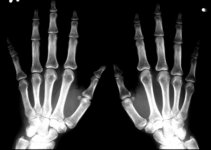

ringensmiskarn skrev:Bröt bägge handlederna och fick gå gipsad i 4 veckor. Ställer till lite problem vill jag lova. Tur man har en förstående fru som hjälpte till med de alldagliga bestyren![]()

Jo det gör det. Körde in i en bil som svängde ut mitt framför mig på mopedtiden. Så dom fick gipsa där i förebyggande för det tog en vecka innan dom kunde se om den var bruten (båtbenet då)twinner skrev:Trist..Men sitter inte båtbenet i handen?

Det är för övrigt min enda vurpa med hoj (hittills).jo de gör de.. ett av de svåraste benen att läka enligt läkarna.. var gipsad i 3 månader!twinner skrev:Trist..Men sitter inte båtbenet i handen?

Showtime skrev:jo de gör de.. ett av de svåraste benen att läka enligt läkarna.. var gipsad i 3 månader!